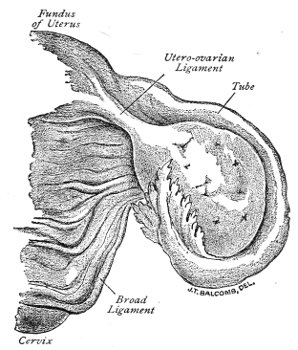

An accurate knowledge of the anatomy and mechanism of the female perineum is essential to an understanding of the nature and treatment of injuries to this structure. The anatomical structures lying between the anus behind and the symphysis pubis in front are those that most directly interest the gynecologist. Proceeding from 57 below upward, we find the following structures lying in superimposed planes: the skin, the superficial fascia, the deep layer of the superficial fascia, the transversus perinæi and the sphincter vaginæ muscles, the anterior layer of the triangular ligament, the posterior layer of the triangular ligament, the levator ani muscle (Fig. 19).

Fig. 18, A.—Superficial structures of the female perineum (Weisse).

Fig. 19.—Dissection of female perineum: on the left side the perineal muscles are exposed by the reflection of the perineal fascia; on the right side the muscles and the superficial layer of the triangular ligament have been removed, thereby exposing the deep layer of the ligament. S. V., Sphincter vaginæ muscle.

The vagina passes through these structures. They surround and support the ostium vaginæ as the fascia and muscles surround and support the opening of the rectum or the anus. The muscles and fasciæ are attached in the median line between the anus and the vagina, and therefore this part of the body, which is called the perineum, is supported or maintained in its 58 proper position by these various structures. The transversus perinæi arises from the ramus of the ischium and is inserted in the perineum. The bulbo-cavernosus, or sphincter vaginæ, arises in the perineum and is inserted in and about the clitoris. The inner fibers of the levator ani arise from the symphysis pubis and are inserted in the perineum and the lower part of the vagina (Fig. 20). When these muscles contract, their action, therefore, is to draw the perineum upward and forward. At the same time the anus is drawn upward and forward, and so also is the posterior margin of the ostium vaginæ and the lower portion of the posterior vaginal wall.

Fig. 20.—Dissection of female perineum, showing the deeper structures after removal of the levator and sphincter ani muscles.

The vagina has no circular sphincter like the anus, but 59 the vaginal month is kept closed by the action of the transversus perinæi, sphincter vaginæ, and levator ani muscles, which draw the perineum forward, and thus keep the posterior vaginal wall in apposition with the anterior wall.

Fig. 21.—Muscular floor of the pelvis seen from above.

This sling of muscles and fascia, which surrounds and supports the opening of the vagina, may readily be felt in the nulliparous woman by introducing the finger in the vagina and pressing backward and outward toward the ischio-rectal fossa. We then feel plainly, immediately within the ostium vaginæ, a firm resisting band of tissue, apparently about half an inch broad, embracing the posterior portion of the lower vagina. This band is formed by the inner edges of the various muscles and planes of fascia that have been described.

Fig. 22.—Sagittal section showing relations of the several layers of fascia within the pelvic floor (Dickinson).

The vagina extends, as a transverse slit in the pelvic floor, upward and backward, approximately in the direction 60 of a line drawn from the ostium vaginæ to the fifth sacral vertebra. It is approximately parallel with the conjugate of the brim, so that when the woman is erect the long axis of the vagina is inclined at an angle of 60° to the horizon. The vagina is not a vertical open tube: it is a slit in the pelvic floor, in health always closed by the accurate apposition of the anterior and posterior walls (Fig. 21). The anterior vaginal wall is about 2½ inches long in a vertical mesial line. The posterior vaginal wall is about 3½ inches long. The vaginal walls are triangular in shape, being broader above than below. The shape of the normal vagina at the pelvic outlet is shown by Fig. 23. The section here shows the vaginal 61 slit of the shape of the letter H. The portions of the slit extending backward and somewhat outward are called the vaginal sulci or furrows. They are directions of diminished resistance in which tears are liable to occur.

Fig. 23.—Section illustrating the characteristic form of the vaginal cleft (Henle): Ua, urethra; Va, vagina; L, levator ani; R, rectum.] 62